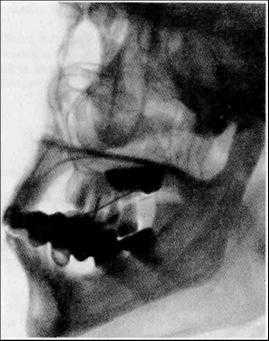

Интерпретация сиалограммы зависит не только от квалификации врача. Известно, что для репрезентации структурно-пространственной организации слюнных желез СГ следует выполнять в боковой проекции. Однако при этом изображение железы проецируется на кости лицевого скелета. Решить данную проблему предлагали за счет рентгенографии в специальной косой проекции [4], ортопантомосиалографии [10] и введения в клетчатку вокруг желез кислорода или закиси азота [2, 6]. Первые варианты не получили распространения, а пневмосиалография оказалась опасной. Данная проблема была решена только с появлением дигитальной субтракционной СГ, которая позволяет с помощью специальной программной обработки убирать или вычитать костный фон из-под контрастного изображения железы.

Стоит признать, что возможности совершенствования аналоговой СГ на данный момент исчерпаны. Однако с переходом на цифровую аппаратуру появилась технологическая возможность решить проблемы СГ и превратить ее в прецизионный метод диагностики. Еще с 70-х годов XX столетия СГ начали выполнять на цифровом ангиографе [33—35]. С появлением дигитальной СГ (от англ. digital — цифровой) был решен основной недостаток аналоговой СГ, связанный с количеством контраста, так как его введение стали осуществлять под флюороскопическим контролем. Затем информацию можно уточнять при анализе видеоизображения. Из возможных вариантов можно выбрать и отпечатать наиболее диагностически значимые сиалограммы (см. рисунок). Решена и проблема анализа контрастного изображения, так как программа позволяет «удалить» из-под изображения железы подлежащий фон в виде костей лица. В таком виде метод получил название дигитальной субтракционной сиалографии (от англ. subtraction — вычитание). Преодолен основной недостаток аналоговой СГ — статичность изображения. На экране монитора и в записи можно наблюдать не только процесс контрастирования, но и эвакуацию контраста после экстубации, что определяет данный метод исследования СЖ как функциональный.

Дигитальная СГ позволила вывести диагностику заболеваний СЖ на принципиально иной уровень информативности. При слюннокаменной болезни можно исследовать движение конкремента по протоку и, таким образом, проводить дифференциальную диагностику с дефектами наполнения иного происхождения. Например, участки слизи при прохождении через более узкие участки и стриктуры изменяют свою форму, а воздух распадается на мелкие пузырьки и постепенно исчезает. Установлено, что эктазии протоков на разных этапах контрастирования могут иметь разный диаметр и разную форму. Симптом размытости изображения протоков и округлых сиалоэктазов при синдроме Шегрена не столь очевиден, как было принято считать раннее. По всей видимости, возможна гипердиагностика из-за невысокого качества аналоговых сиалограмм. Появилась возможность исследовать мелкие детали контрастного изображения, которые раннее были недоступны для анализа. Оказалось, что дефекты контрастирования паренхимы, которые соответствуют объемным образованиям, по-разному интерпретируются в зависимости от этапа наполнения протоков и паренхимы. И зачастую совсем необязательно для этого контрастировать паренхиму. Большей информативностью могут обладать СГ на этапе заполнения протоков. Возможность изучить процесс эвакуации контрастного препарата после экстубации превращает СГ в функциональный метод исследования, дифференциальные возможности которого еще предстоит изучить [22, 25, 26].